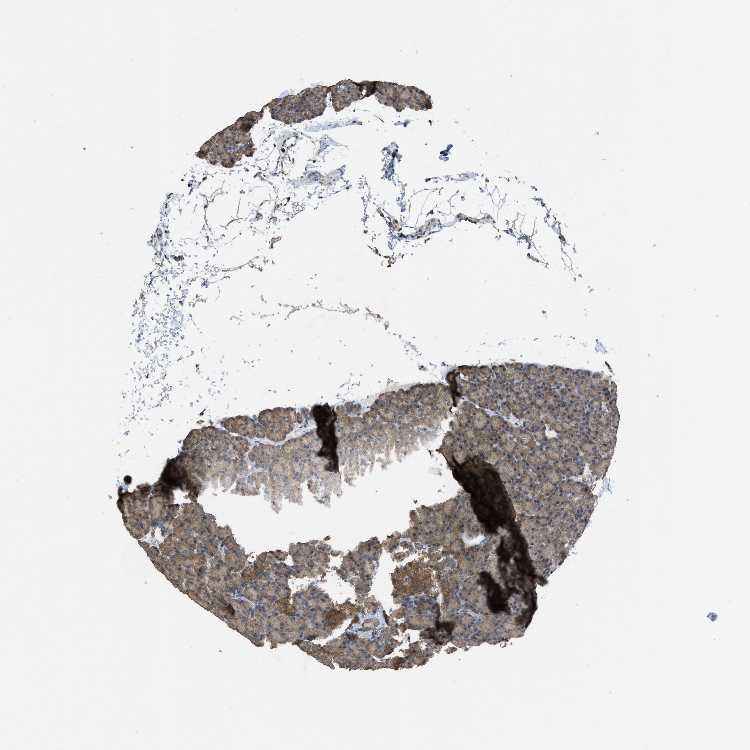

PANCREAS - Antibody stainingi

Antibody staining in the annotated cell types in the current human tissue is reported as not detected, low, medium, or high, based on conventional immunohistochemistry profiling in selected tissues. This score is based on the combination of the staining intensity and fraction of stained cells.

Each image is clickable and will lead to virtual microscopy that enables deeper exploration of all samples and also displays staining intensity scores, fraction scores and subcellular localization as well as patient and tissue information for each sample.

Antibody HPA020994Antibody HPA020996Antibody CAB005035

Exocrine glandular cells LowMediumHigh

Pancreatic endocrine cells MediumMediumLow